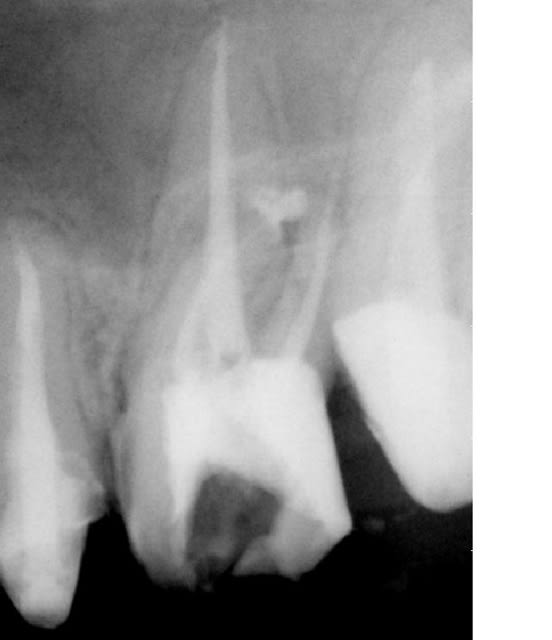

Quand je vois le traitement de Ploc, je trouve qu'il était justifié puisque la dent présente certes une belle lésion périradiculaire, mais a des canaux sans grande anomalie de forme et plutot bien obturés.